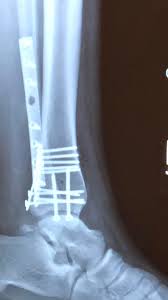

First Time Walking After Ankle Orif Youtube

First Time Walking After Ankle Orif Youtube from i.ytimg.com

When can i walk without crutches? John goldman answered 55 years experience rheumatology good question : 9th week after ankle surgery, and still need 2 crutches to walk with limp. How long do bones take to heal after an ankle break? Most people get the green light from their doctor to slowly start putting weight on their leg around six weeks after breaking their ankle, although this may be less or more depending on your injury. But there's a lot more to the story, a story i wasn't sure i wanted to tell because i'd rather pretend this nightmare never happened. Follow up to the office 5 to 7 days after surgery. I was able to walk on my own 20 days after the doctor said i was allowed to walk.